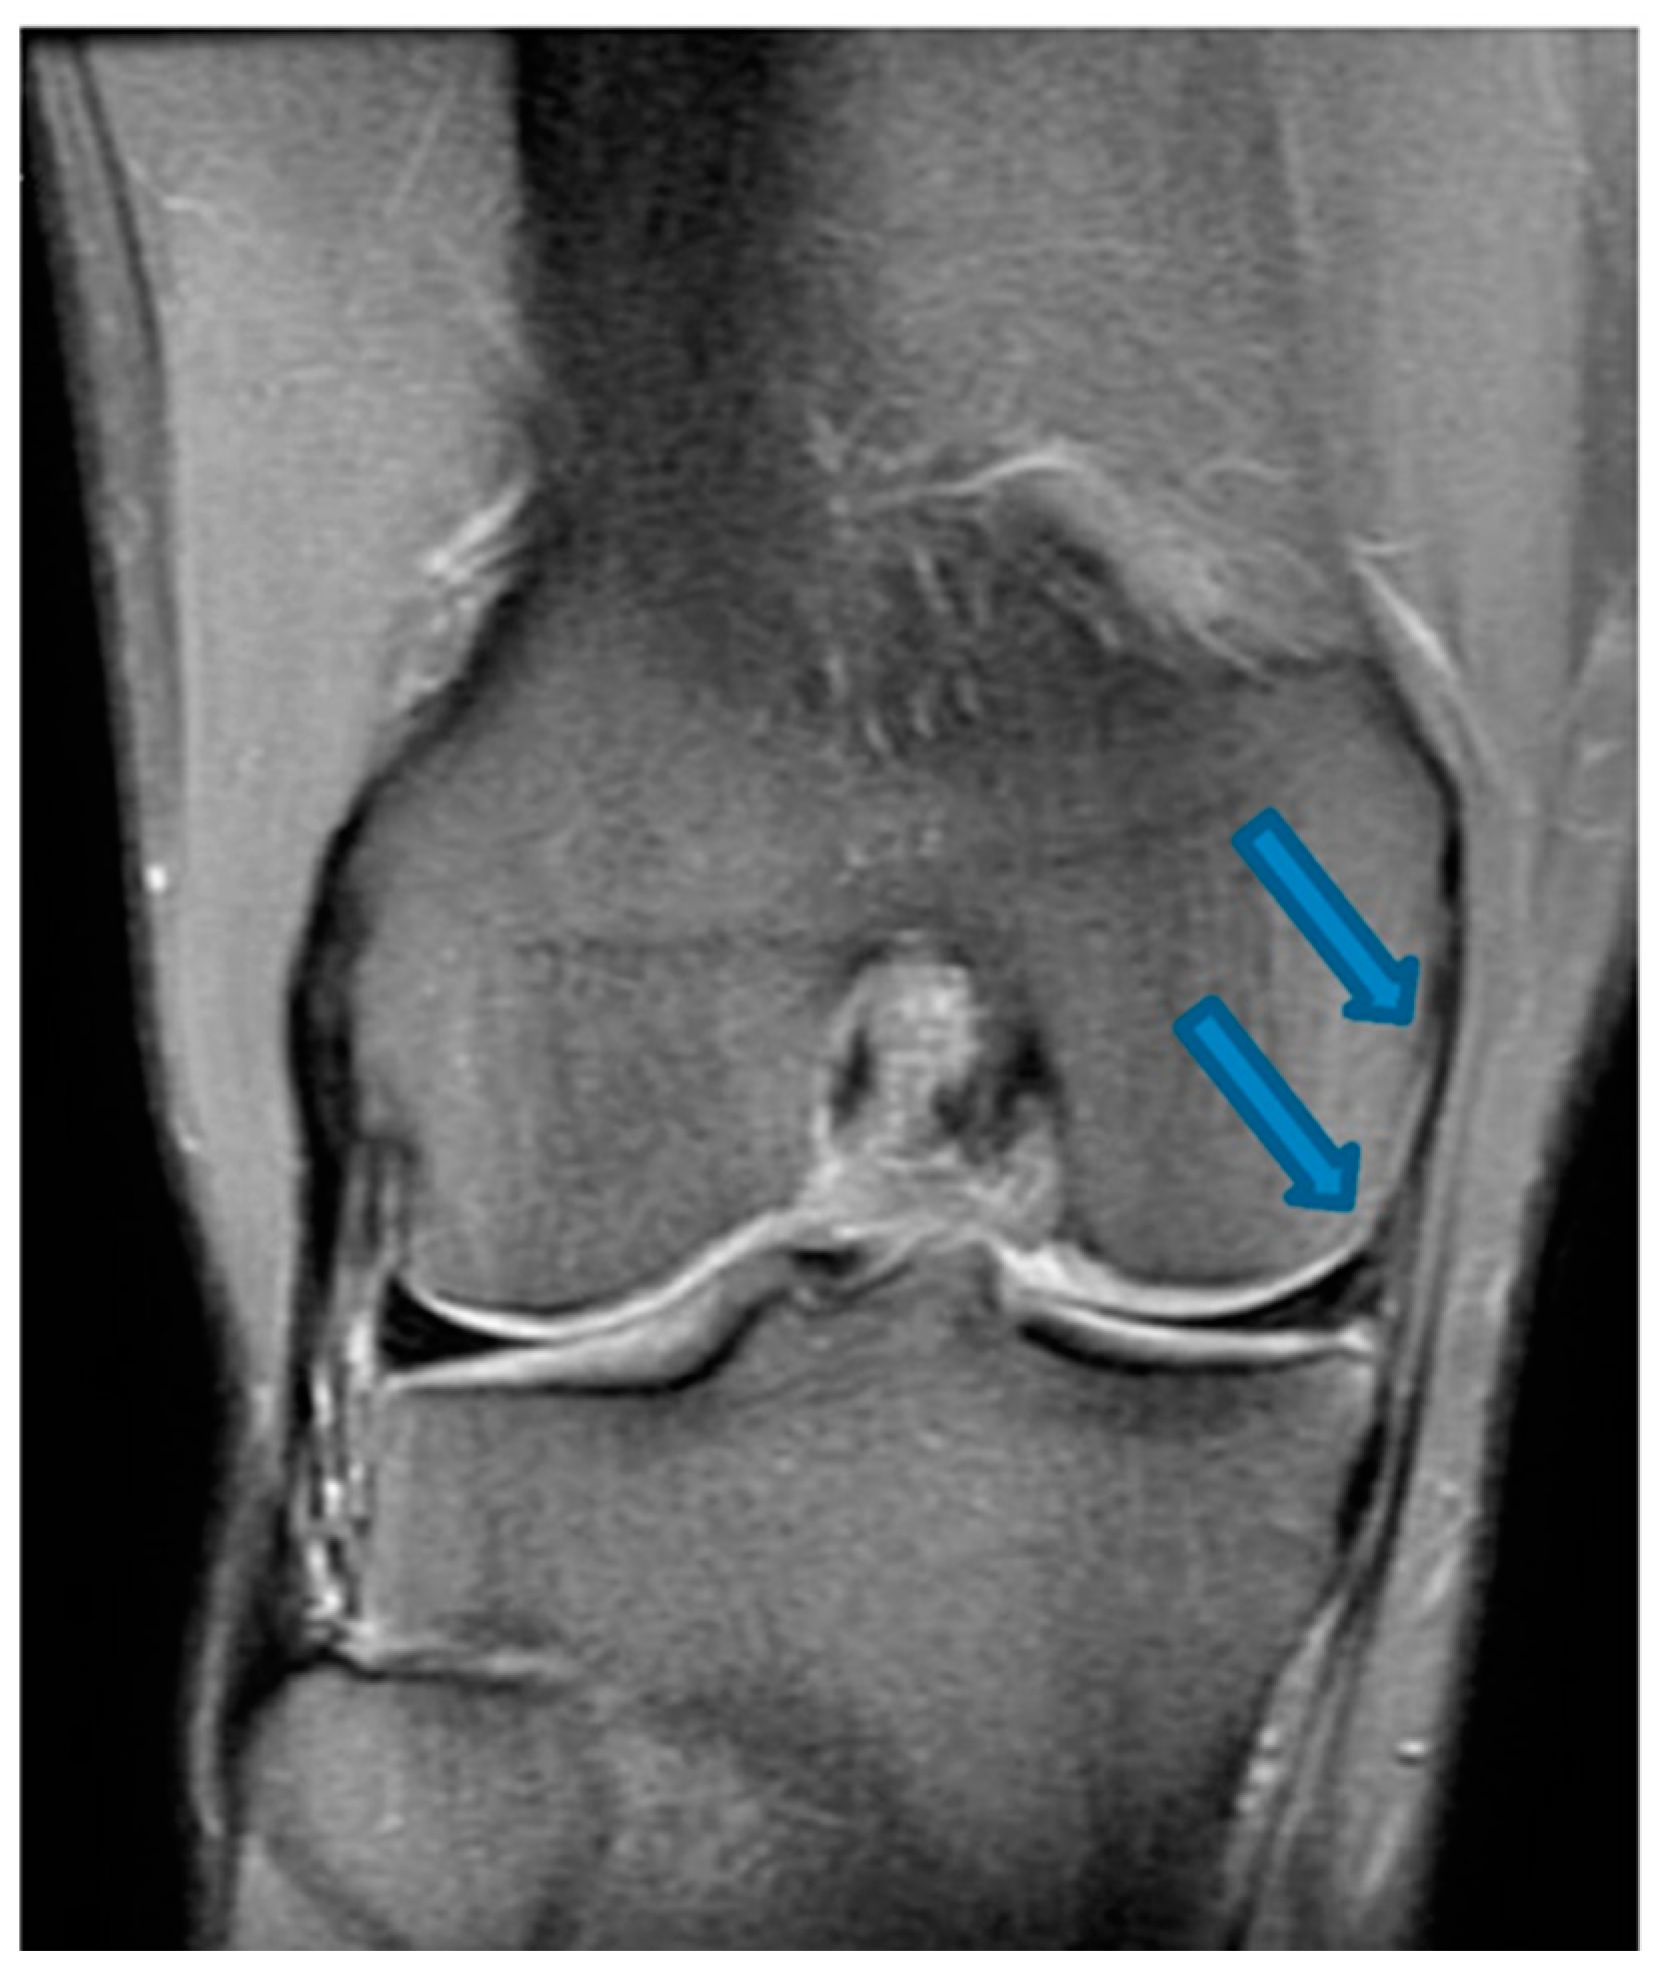

| 24 December 2021 | MRI scans confirming signs of complete ACL, MCL and medial meniscus healing |